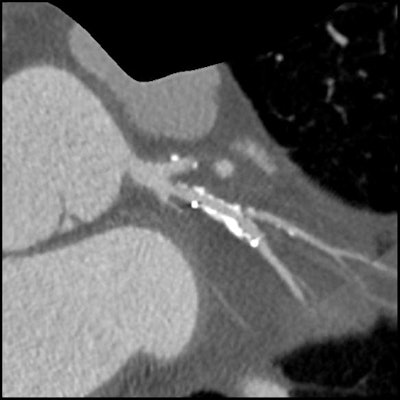

Image series shows comparison images demonstrating how high-definition CTA improved reporting accuracy. Case is a 49-year-old man with previous stent to the circumflex artery with recurrent pain. Left: Image shows a stent in the circumflex artery but no stenosis. Right: Image shows an occluded right coronary. All images courtesy of Dr. Carl Roobottom."My analogy would be a conventional detector is like an energy-saving light bulb, so we turn it on and off very quickly, [and] you still get some light in the background, whereas the gemstone is a bit more like a flashlight so acts like a strobe," he said.

Same patient as above. Image shows the circumflex but demonstrates how use of the Discovery HD750 scanner allows clear visualization of the short stenosis despite the stent and high level of calcium in the arteries.At Roobottom's institution, they run the HD scanner in both modes depending on the calcium score. Low calcium scores receive conventional imaging, while high calcium scores receive HD imaging.

"Does it work? It certainly gives us more confidence," Roobottom said. During his ISCT presentation, he illustrated several cases in which multiple stenoses were identified that "might have been missed" if the HD setting hadn't been used. HD also identifies stents, native vessels, and reduces blooming artifacts.